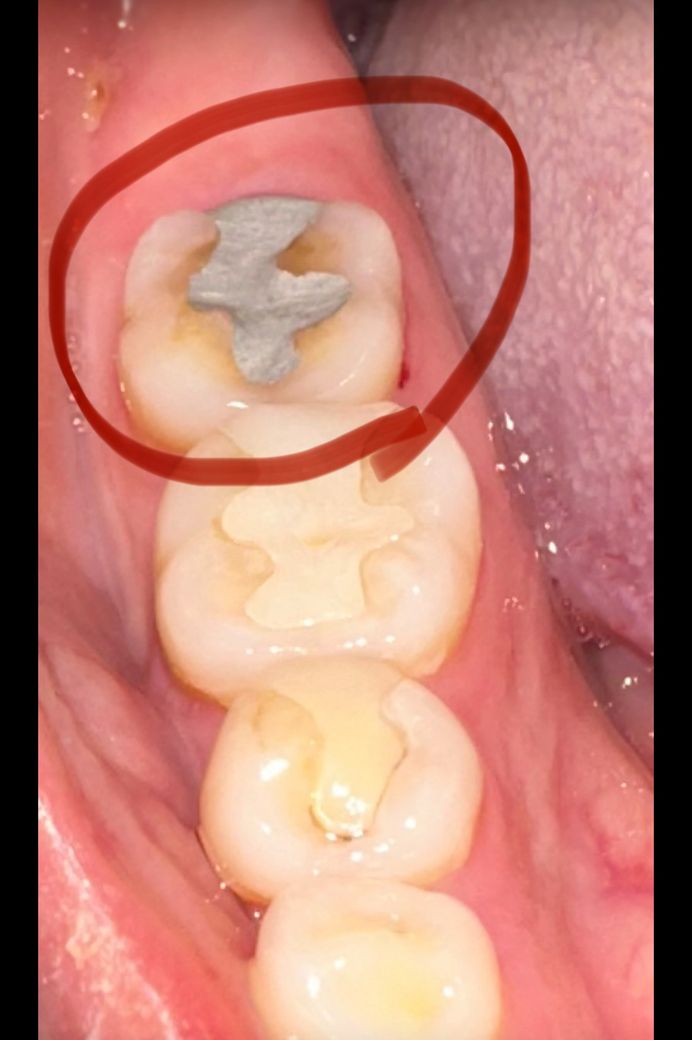

어금니로 떼운데 떨어져서 아말감으로 떼웠어요 이빨을 긁어내서 그런건지 씹을때 찌릿한 통증이 있어요 말할때도 바로 위 어금니가 덮어씌운건데 부딪혀서 그러는지 찌릿한 통증 있더라고요 치료한지 이틀 됐는데 지금은 조금 통증이 덜 하긴 해요 혹시 이상태에서 술 마시면 염증 생기거나 그럴까요?

• 1번 째 사진